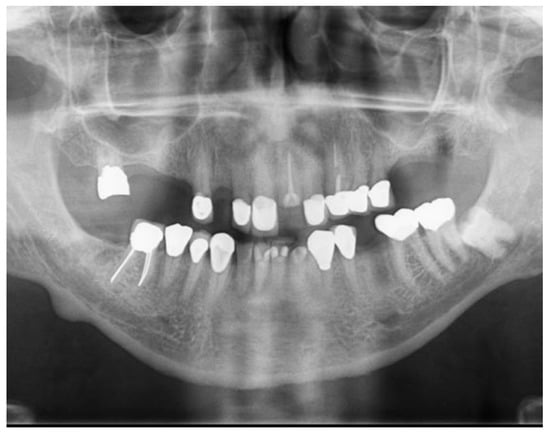

Full-Mouth Rehabilitation of a Patient with Sjogren’s Syndrome with Maxillary Titanium-Zirconia and Mandibular Monolithic Zirconia Implant Prostheses Fabricated with CAD/CAM Technology: A Clinical Report

2. Materials and Methods